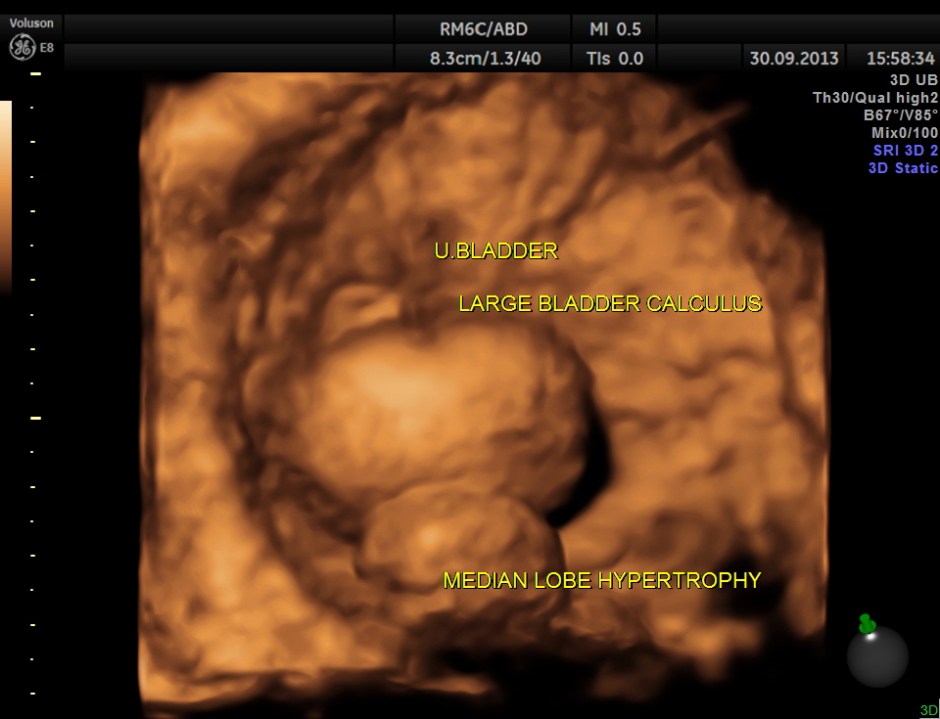

urinary bladder showed a large calculus and prominent swelling of the median lobe of the prostate.

multi- planar view of the bladder calculus

2 D and 3 D views of the median lobe hypertrophy

The diagnosis given was Large calculus in the urinary bladder , Severe prostatic enlargement with prominent median lobe hypertrophy , causing Right sided obstructive uropathy.

The diagnosis was made with the 2D images , but the 3 D images were very helpful in explaining to the patient.